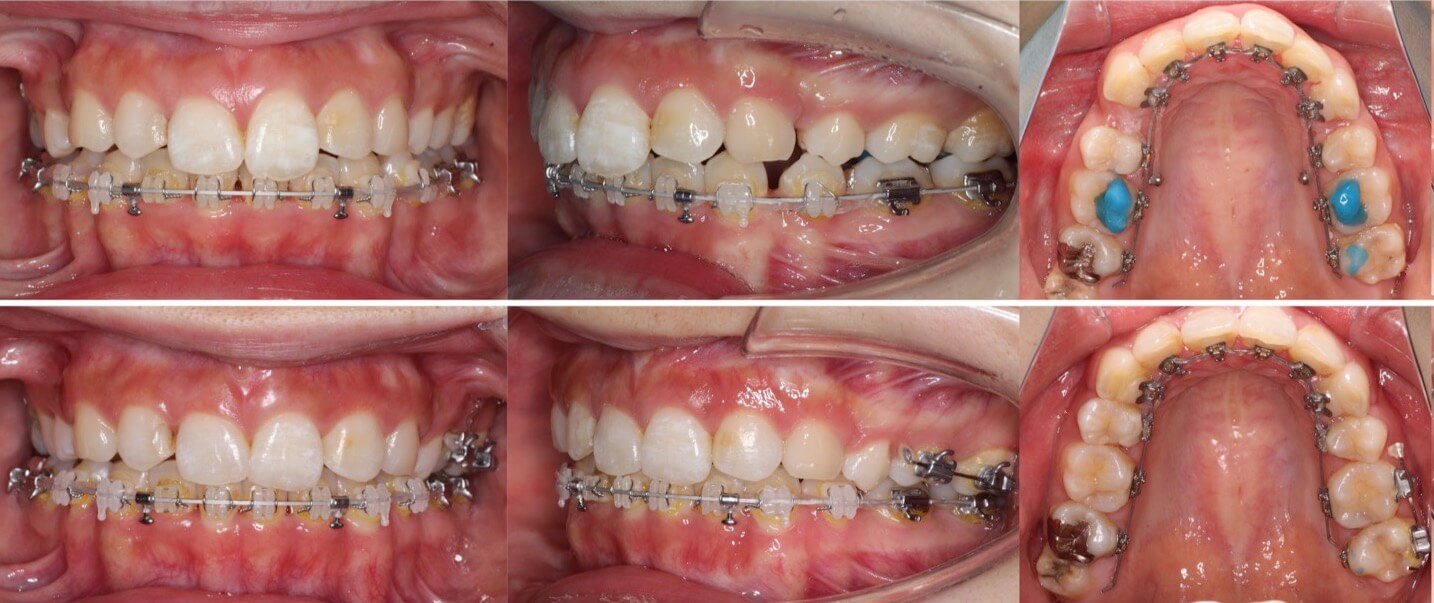

20代女性・唇側矯正装置・2本抜歯

重度の過蓋咬合であったため、唇側ワイヤー矯正装置とアンカースクリューにより、先に上の前歯の圧下(歯茎方向への移動)を行なった後に、ゆっくりと抜歯空隙を閉鎖しました。このように過蓋咬合では前歯に植立するアンカースクリューがあった方が治療が効率的に進みます。

<症例概要>

主訴:前歯の突出と噛み合わせ

年齢・性別:20代女性

住まい:東京都練馬区

症状:過蓋咬合・上顎前突

治療方針:上顎前歯の圧下・抜歯空隙の閉鎖

治療装置:唇側矯正装置

固定装置:歯科矯正用アンカースクリュー(上唇側x2)

抜歯:上左右第一小臼歯(計2本)

治療期間:2年6か月

リテーナー:下フィックスタイプ+上下プレートタイプ

治療費用:968,000(税込)

代表的副作用:痛み・治療後の後戻り・歯根吸収・歯髄壊死・歯肉退縮

▶︎その他の副作用